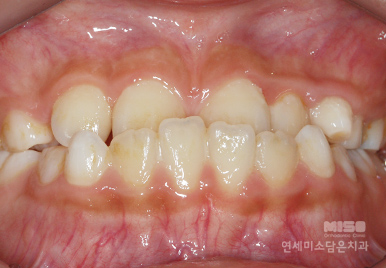

Before